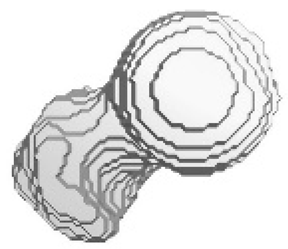

5.2. Comparison and Similarity of 3D Reconstruction Images

| Isometric View of the Left Femur | Ground Truth and Predicted Results of the Left Femur under Dataset Category F-I | |||||

|  | Front | Left | Rear | Right | Top | Bottom |

| Ground Truth |  |  |  |  |  |  |

| Prediction |  |  |  |  |  |  |